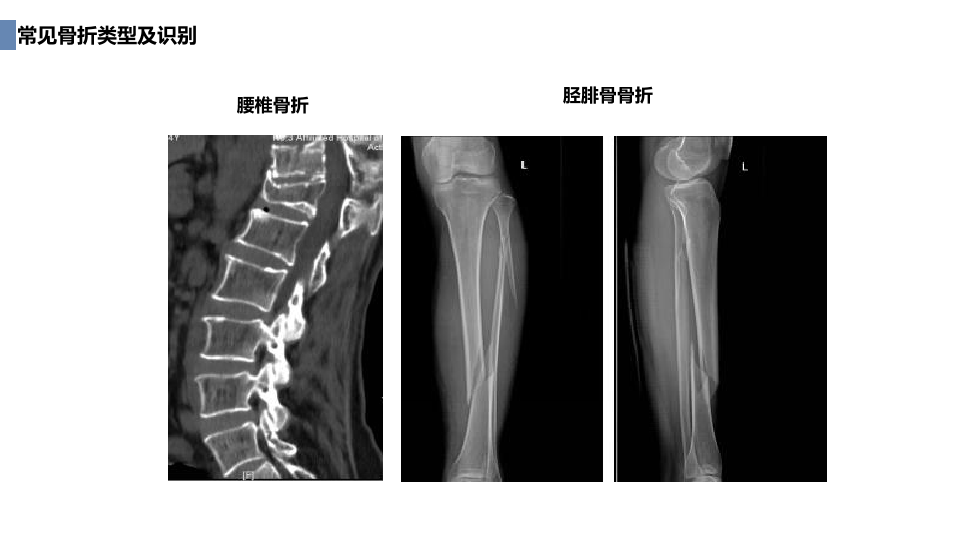

创伤骨科急救